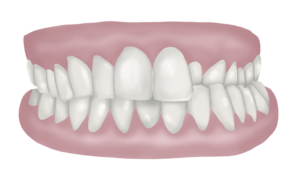

En aquest camp és on trobem les diferents maloclusions o tipus de mossegada desequilibrada.

Podem classificar-ho de la següent manera:

. En el pla frontal podem trobar:

Mossegada oberta

La mossegada oberta la reconeixem perquè les dents de dalt no contacten amb les de baix, això es pot donar a nivell anterior o bé a nivell lateral/posterior de l’arcada dentària.

Sobremossegada

La sobremossegada es caracteritza perquè les dents del maxil·lar superior recobreixen en excés les del maxil·lar inferior. En alguns casos les del maxil·lar inferior estan completament ocultades per les del superior (no es veuen els incisius inferiors, de vegades aquests poden inclús impactar a la geniva del paladar quan tanquem).

Classe II Molar

La classe II molar es dona quan la mandíbula està excessivament retruïda respecte el maxil·lar. Avaluem els mil·límetres de retrusió agafant com a referència la posició dels primers molars definitius .

Classe III Molar

En la classe III molar trobem una mandíbula excessivament avançada respecte el maxil·lar. També prenem els primers molars definitius com a punt de referència per avaluar la complexitat del cas.

Apinyament

Es dona quan les dents no tenen prou espai per col·locar-se alineades i les trobem les unes recobrint parcialment les altres, com «encavallades».

Abanicament

Quan veiem que les dents estan excessivament «obertes» com un «vano» , mirant cap a l’exterior de la boca, en alguns casos fins i tot hi poden haver diastemes (separacions entre una dent i l’altra)

Mossegades creuades

La mossegada creuada es dóna quan a l’hora de tancar la boca i apretar les dents, les dents maxil·lars (superiors) estan per dins de les mandibulars (inferiors). Normalment, quan tanquem la boca les dents de dalt han de quedar més cap a fora que no pas les de baix, en aquests casos hi sol haver un dels dos costats on aquesta posició està invertida.